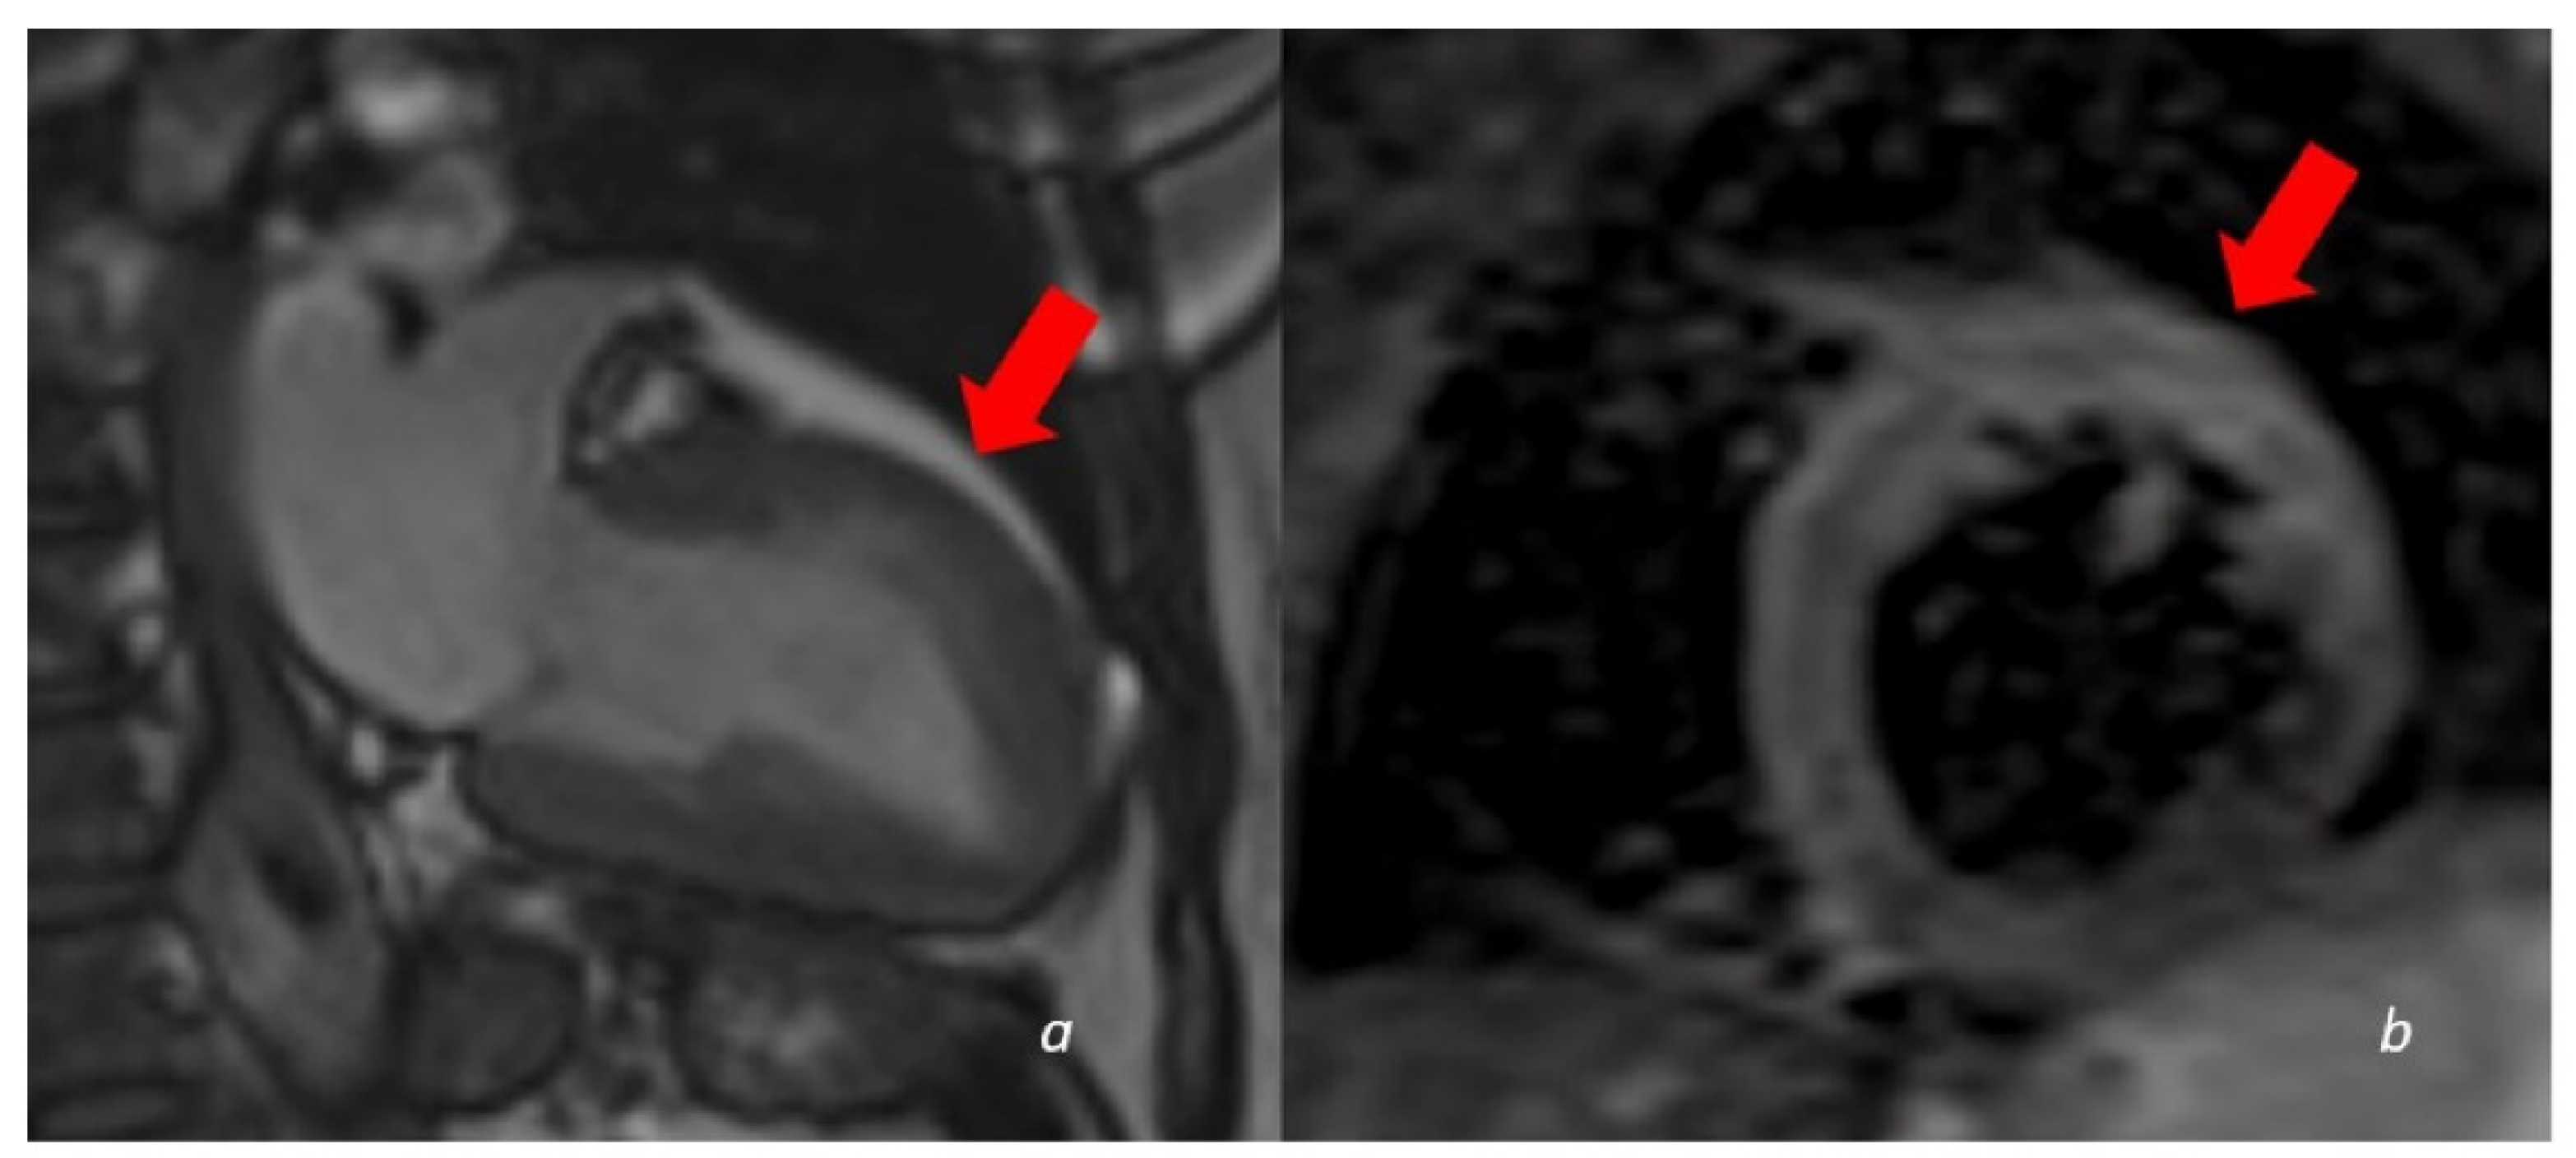

CT and MRI can equally demonstrate pericardial effusion and pericardial thickening. A 4 mm thickness is conventionally indicated as the upper limit of normal, although it must be emphasized that pericarditis may be present even when the pericardium is within normal limits. Stranding of the pericardiac fat tissue can be an ancillary finding [31]. MRI better depicts pericardial enhancement (on spin echo T1 and LGE sequences) and myocardial enhancement, and the combination of the two (myopericarditis) entails a higher risk of complications [32] (Figure 2).

Figure 2. A 28 y/o man presented at the emergency department with fever and chest pain. At the admission, cardiac enzymes were elevated and ECG did not show any alteration. Cardiac MRI was performed 1 day later and revealed pericardial alteration: presence of edema (a) and post-inflammatory fibrosis (b,c).